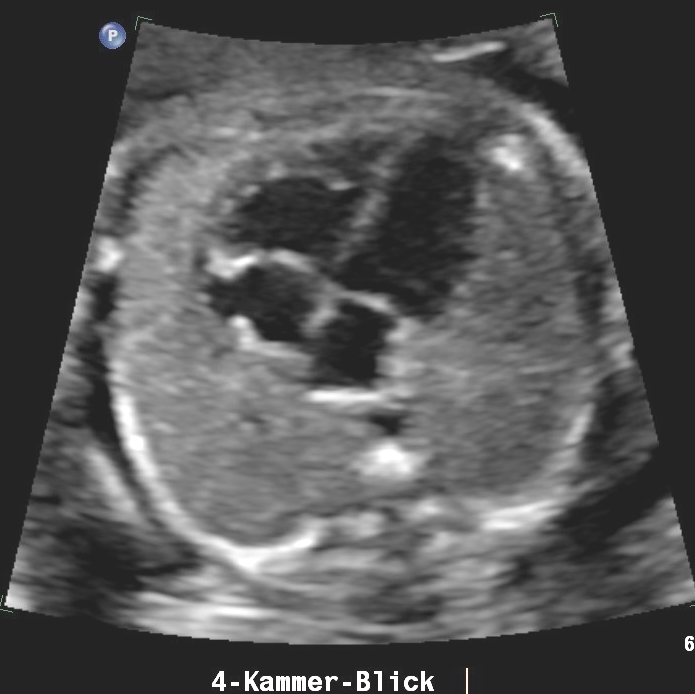

Bildtitel

Button